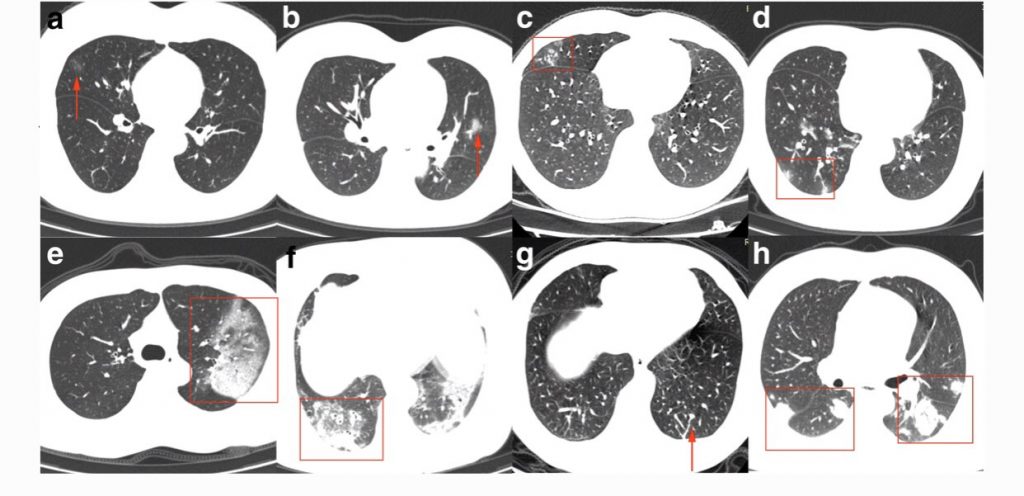

De Koreanen publiceren veel studies.

We krijgen een steeds duidelijker beeld van de verschillende afwijkingen op de foto.

Voor de liefhebber: https://t.co/kFPzWdYzKU pic.twitter.com/bBrav2vUJo— Sander de Hosson (@shossontwits) March 1, 2020